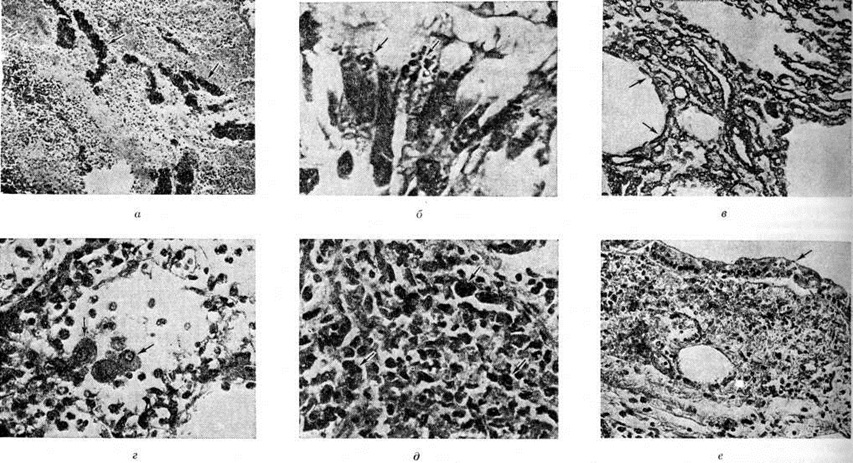

По локализации и объёму поражения лёгких различают следующие формы Пневмония: долевую, или лобарную, Пневмония— при поражении целой доли лёгкого (в этом случае применяют термин «крупозная пневмония»); очаговую Пневмония— при поражении части сегмента, целого сегмента или нескольких сегментов лёгких. В связи с тем, что при очаговой Пневмония обычно поражаются и бронхи, в качестве синонима используется термин «бронхопневмония». Воспалительный процесс при очаговой Пневмония чаще локализуется в нижних долях лёгкого, особенно справа, иногда бывает двусторонним. В случае слияния ряда очагов создаётся впечатление о поражении целой доли (цветной рисунок 1), что обозначается термином псевдолобарная Пневмония (например, при Пневмония, вызванной палочкой Фридлендера). При локализации патологический изменений в строме лёгкого Пневмония называют интерстициальной или межуточной; такие изменения, однако, редко бывают воспалительными в полном смысле слова, как правило, это лимфогистиоцитарно-плазмоцитарные, чаще периваскулярные и перибронхиальные инфильтраты, являющиеся местным проявлением иммунологический реакций. При поражении в основном респираторных отделов лёгких патологоанатомически выделяют альвеолиты — форму Пневмония, характеризующуюся выраженными изменениями альвеолоцитов.

В большей части случаев альтеративный компонент воспаления выражен слабо. Вначале отмечается только полнокровие структурных образований лёгкого, в которых находятся и размножаются бактерии. Вскоре возникает отчётливо выраженная фаза экссудации, которая начинается с выпотевания в полость альвеол плазмы крови — серозной жидкости; затем к ней присоединяется все возрастающее количество нейтрофильных лейкоцитов. При поступлении в очаг воспаления грубодисперсных белков крови происходит выпадение фибрина (рисунок 1). Пролиферативные изменения в подавляющем большинстве острых бактериальных Пневмония выражены незначительно. В том случае, когда бактерии, в частности стафилококки или стрептококки, образуют значительное количество токсинов, возникает некроз клеток экссудата и лёгочной ткани, резко повышается проницаемость кровеносных сосудов.

При пневмококковой Пневмония, в частности при её наиболее тяжёлом варианте — крупозной Пневмония, процесс начинается с развития небольшого очага серозного воспаления, располагающегося обычно в задних или в заднебоковых отделах лёгких, где содержатся пневмококки (рисунок 2, а). Патологический процесс распространяется прежде всего контактным путём и очень быстро захватывает значительную часть лёгкого — целую долю и даже несколько долей. Макроскопически лёгкое увеличено в объёме, его ткань резко отёчна и полнокровна. Эти изменения носят название стадии прилива.

В дальнейшем в экссудате нарастает количество нейтрофильных лейкоцитов, нередко одновременно с фибрином серозно-гнойный экссудат постепенно заполняет просветы альвеол (рисунок 2,6); последние достигают при этом размеров, которые они имеют на вдохе; пневмококки в это время фагоцитируются лейкоцитами и исчезают. При прогрессировании болезни более выраженные нарушения определяются на границе с неизменённой тканью органа. На разрезе лёгкое серого цвета с мелкозернистой или гладкой поверхностью, по консистенции напоминает печень (серая гепатизация лёгкого). У больных с повышенной проницаемостью сосудов к экссудату присоединяется большое количество эритроцитов, в результате чего лёгкое приобретает серо-красный или темно-красный цвет (красная гепатизация лёгкого).

При очаговой пневмококковой Пневмония отмечаются сходные изменения, но с меньшей степенью выраженности.

Стафилококковая Пневмония имеет ряд особенностей. На ранних стадиях заболевания вокруг скоплений стафилококков появляется серозный или чаще серозно-геморрагический экссудат с небольшой примесью нейтрофильных лейкоцитов. В дальнейшем очаги воспаления приобретают характерное зональное строение.

В центре их содержится много стафилококков, возникают некротические изменения (рисунок 3, а), вокруг участков некроза накапливаются лейкоциты, которые фагоцитируют стафилококки. В периферических участках пневмонического очага альвеолы содержат фибринозный или серозный экссудат, в котором нет бактерий. При тяжёлом течении болезни (стафилококковой деструкции лёгких) в местах скоплений стафилококков на значительном протяжении происходит разрушение лёгочной ткани. Макроскопически в лёгких выявляются множественные мелкие, нередко сливающиеся очаги абсцедирующей Пневмония Они красного или темно-красного 4 цвета с желтовато-серыми участками расплавления в центральной части. Позднее здесь формируются абсцессы,. принимающие иногда хронический течение. При распространении инфекционные процесса на плевру и её деструкции возникает сообщение между полостью абсцесса, бронхами и плевральной полостью, развивается пиопневмоторакс (смотри полный свод знаний). Иногда в результате деструкции стенки бронха и проникновения воздуха в интерстиций возникает интерстициальная эмфизема.

Стрептококковая Пневмония имеет много общих черт со стафилококковой. Однако в тяжёлых случаях она характеризуется большей степенью некроза клеток экссудата и лёгочной ткани, а также более выраженной лимфогенной генерализацией процесса.

Для Пневмония, вызванной синегнойной палочкой, также типичен некроз клеток экссудата и лёгочной ткани, особенно в центре пневмонического очага, где видны скопления бактерий. По периферии очага отмечаются выраженные нарушения кровообращения.

Очаги Пневмония, вызванной палочкой Фридлендера, могут иметь долевой характер. Экссудат, а также выделяемая больным мокрота носят слизеподобный характер, поскольку палочка Фридлендера имеет слизистые капсулы; из-за небольшого содержания фибрина поверхность разреза лёгкого обычно гладкая. Характерно также образование обширных инфарктообразных некрозов лёгочной ткани в связи с тромбозом сосудов лёгкого. Макроскопически пневмонические очаги серовато-розового или реже серого цвета, нередко с красными участками кровоизлияний.

Для Пневмония при острых вирусных респираторных инфекциях (гриппе, парагриппе, респираторно-синцитиальной и аденовирусной) наиболее характерно поражение эпителия слизистой оболочки дыхательных путей и альвеолоцитов. В результате внутриклеточного размножения вирусов происходит повреждение этих клеток с развитием дистрофических и некротических изменений. При благоприятном течении заболевания через несколько дней в них возникают реактивные изменения в виде уплотнения цитоплазмы вокруг участка повреждения — фуксинофильные включения) (рисунок 3, б). Наряду с этим наблюдаются умеренно выраженные воспалительные изменения слизистой оболочки дыхательных путей с преобладанием нарушений кровообращения в виде полнокровия сосудов, выпотевания серозной жидкости в просвет альвеол и небольших кровоизлияний. Отмечаются также небольшие скопления нейтрофильных лейкоцитов и альвеолярных макрофагов. В результате нарушения образования сурфактанта (смотри полный свод знаний) возникают небольшие ателектазы (смотри полный свод знаний), большей частью неполные,— дистелектазы (рисунок 3, в), что особенно выражено у детей раннего возраста, а также компенсаторное очаговое расширение альвеол в других участках лёгких. Макроскопические изменения при этом незначительны и заключаются в основном в катаральном воспалении дыхательных путей и образовании в лёгких небольших участков уплотнения темно-красного или синюшного цвета. Наиболее характерной чертой вирусной Пневмония является гигантоклеточное превращение поражённых эпителиоцитов.

При гриппе поражённые клетки несколько увеличиваются в объёме, в случае же отторжения превращаются в крупные одноядерные клетки, значительно превышающие по размерам обычные альвеолярные макрофаги (рисунок 3, г). Для парагриппа типичны подушкообразные разрастания, сосочковидные выросты слизистой оболочки. При респираторно-синцитиальной инфекции они ещё более выражены. При аденовирусной Пневмония происходит образование крупных одноядерных клеток (гигантоклеточный метаморфоз альвеолоцитов), а также выраженное накопление экссудата (рисунок 3, д). При выздоровлении происходит регенерация эпителия дыхательных путей. Вначале выявляются недифференцированные уплощённые эпителиальные клетки, располагающиеся обычно в несколько рядов (рисунок 3, е), которые в дальнейшем дифференцируются .

Изменения, сходные с морфологический изменениями при вирусной Пневмония, наблюдаются при микоплазменной Пневмония — респираторном микоплазмозе (смотри полный свод знаний Микоплазменные инфекции). Для неё также типично внутриклеточное размножение возбудителя (рисунок 4), хотя возможно и внеклеточное. Поражения носят характер десквамативной Пневмония при весьма умеренных макроскопических изменениях (цветной рисунок 3—5; 6—10).